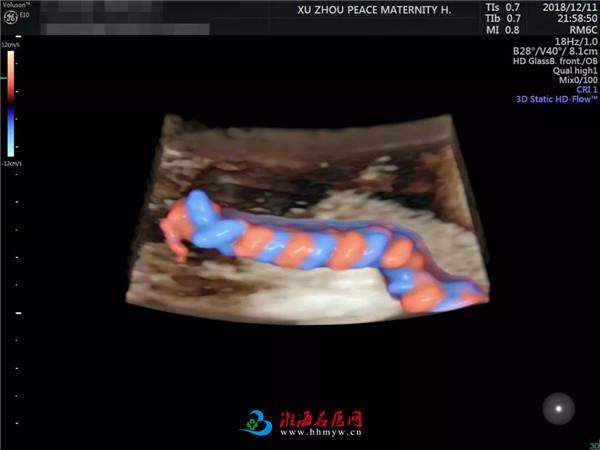

你如果看过邱博士做出的彩超图片

就明白为啥预约这么火爆了

邱博士细致、严谨的工作态度再加上

操作美国GE-E10彩超设备的精湛技术

胎儿神经系统、心脏结构异常等各类胎儿畸形筛查,尤其擅长对复杂疑难病症的产前超声诊断。